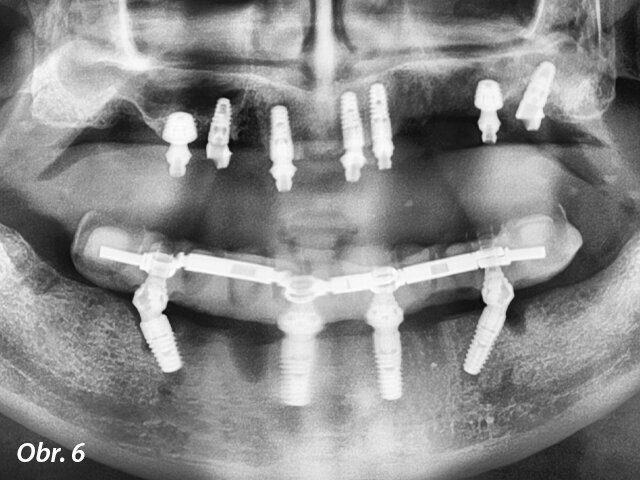

Zavádění ultrakrátkého implantátu do distálního úseku horní čelisti.

Následně byl odklopen mukoperiostální lalok v rozsahu celého horního oblouku. Byl proveden pečlivý „debridement“, při němž byly odstraněny všechny zánětlivé a fibrózní tkáně a obnaženy všechny kostní defekty. Následně byly pomocí kostních dlátek a kulatých frézek vytvarovány mělké kostní defekty, zatímco hluboké defekty byly vyplněny xenoštěpem (Geistlich Bio-Oss, Geistlich Biomaterials) a překryty vstřebatelnou membránou (Geistlich Bio-Gide, Geistlich Biomaterials). Ve frontálním úseku byly zavedeny standardní implantáty (blueSKY, bredent medical), a zároveň byly v místech prvních molárů umístěny dvě fixtury 5,2 × 6,0 mm (copaSKY, bredent medical) (obr. 5). Z důvodu maximalizace primární stability ultrakrátkých implantátů byla zvolena vnitřní osteotomie k bikortikálnímu ukotvení implantátů. Fixtury nepronikly do sinu, ani nebyla patrná elevace sliznice sinu. Všechny implantáty dosahovaly primární stability ≥ 35 Ncm. Panoramatický RTG snímek pořízený na konci chirurgického zákroku prokázal správné umístění implantátů (obr. 6).